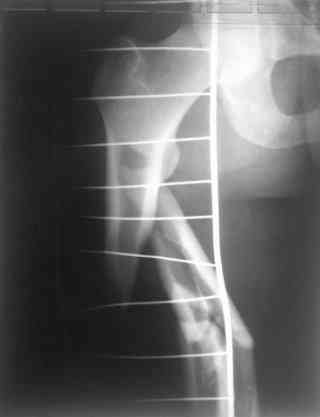

молодй человек 26лет получил С3-перелом правого бедра и легкую черепно мозговую травму (сотрясение головного мозга). Через неделю (противошоковые мереприятия и скелетное вытяжение выполнялось в ЦРБ)оперирован: БИОС бедра стержнем СнМ, Польша. Выписан со швами на амбулаторное лечение по месту жительства в г. Ижевск.Через 1месяц главным врачом больницы, со слов пациента, предложен реостеосинтез пластиной "соберем кость".

Надеюсь сейчас показать перелом, а потом синтез.

Про "кролика", конечно, не очень хорошо с точки зрения деонтологии. Но коллега, Вы думаете кто-нибудь из заядлых Nailer- ов оценит положительно этот остеосинтез? Возможно, на то были объективные причины: отсутствие штифтов большего диаметра..., штифтов, позволяющих блокировать более толстыми винтами..? А уж Plater-ы, конечено засмеют.

У данного пациента есть все основания ожидать несращения. Менять штифт (безусловно тонкий и недостаточно стабильный для этого перелома) на пластину не лучший вариант, особенно, если предполагается открытая операция. Или главный врач в Ижевске имеет ввиду длинную мостовидную пластину LCP по технике MIPO? Тогда шансов на сращение будет больше, чем сейчас, но с нагрузкой придется очень и очень подождать.

Мы бы сейчас перештифтовали : удалить, рассверлить, и забить штифт 13-16 мм диаметром и на пару см. подлиннее. Предпочтительнее штифт, имеющий изгиб во фронтальной плоскости в проксимальном отделе для введения через верхушку б\вертела и имеюший возможность проксимального блокирования по оси шейки бедра.